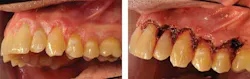

A differential diagnosis was made in this case with a possibility of proliferative verrucous leukoplakia (PVL) based on the clinical appearance and lack of a firm etiology (see Figure 1). A biopsy was performed and a diagnosis of benign hyperkeratosis without dysplasia was rendered.

Laser surgery was performed in this case to remove the long-standing questionable tissue and to prevent further progression of any diseased tissue (see Figure 2). The white plaques are clinically indistinguishable from any typical leukoplakia, but they do exhibit a verrucous texture in most cases. Reported cases of early hyperkeratosis with progression to PVL are documented in the literature.

PVL of the gingiva has been suggested as a subset of proliferative verrucous leukoplakia (Fettig et al. 2009), targeting the specific tissue of the gingiva. Both the free and attached gingiva have been reported in these cases of PVL. Figures 3 and 4 depict a patient who was diagnosed with PVL (Figure 3) and suffered a recurrence of PVL (Figure 4) that was even more intense, with subsequent development of SCC.

Figure 1: Patient presents with clinical characteristics of PVL (courtesy of Dr. Thomas Caputo). Figure 2: Laser treatment of the affected area seen in Figure 1 (courtesy of Dr. Thomas Caputo). Figure 3: Proliferative verrucous leukoplakia before removal (courtesy of Dr. T.D. Rees). Figure 4: PVL after removal as seen in Figure 3. Recurrence with intense exophytic lesions during later diagnosis of SCC (courtesy of Dr. T.D. Rees).